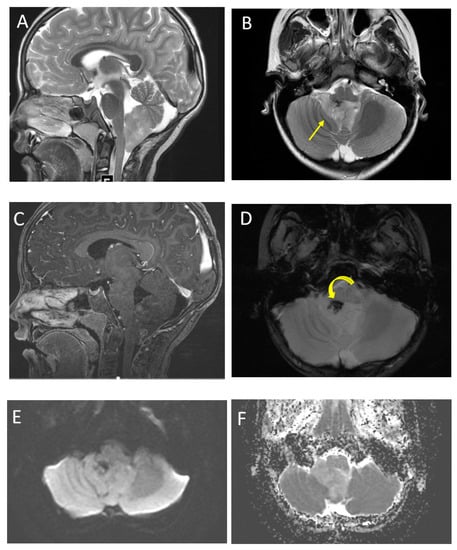

| Posterior fossa ependymoma | Fourth ventricle (PFB) or cerebellopontine angle (PFA) | Heterogeneous mass Calcifications common Intermediate diffusion (between medulloblastoma and pilocytic astrocytoma) Usually enhancing High myo-inositol on MRS |

| Supratentorial ependymoma | Frontal or parietal parenchyma | Large mass with necrosis Central chunky calcifications Diffusion restriction in two-thirds |